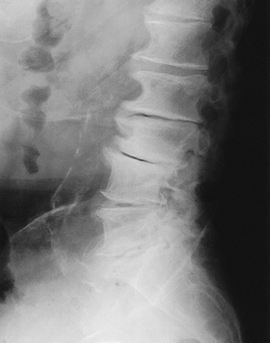

FIGURE 3-38 Flexion (A) and extension (B)

radiographs demonstrating anterior subluxation of L5 on S1. The degree of subluxation is determined by dividing the lower vertebral endplate into four equal segments. Subluxation is graded 1 to 4. In this case, it is Grade 1 and reduces slightly with extension. |